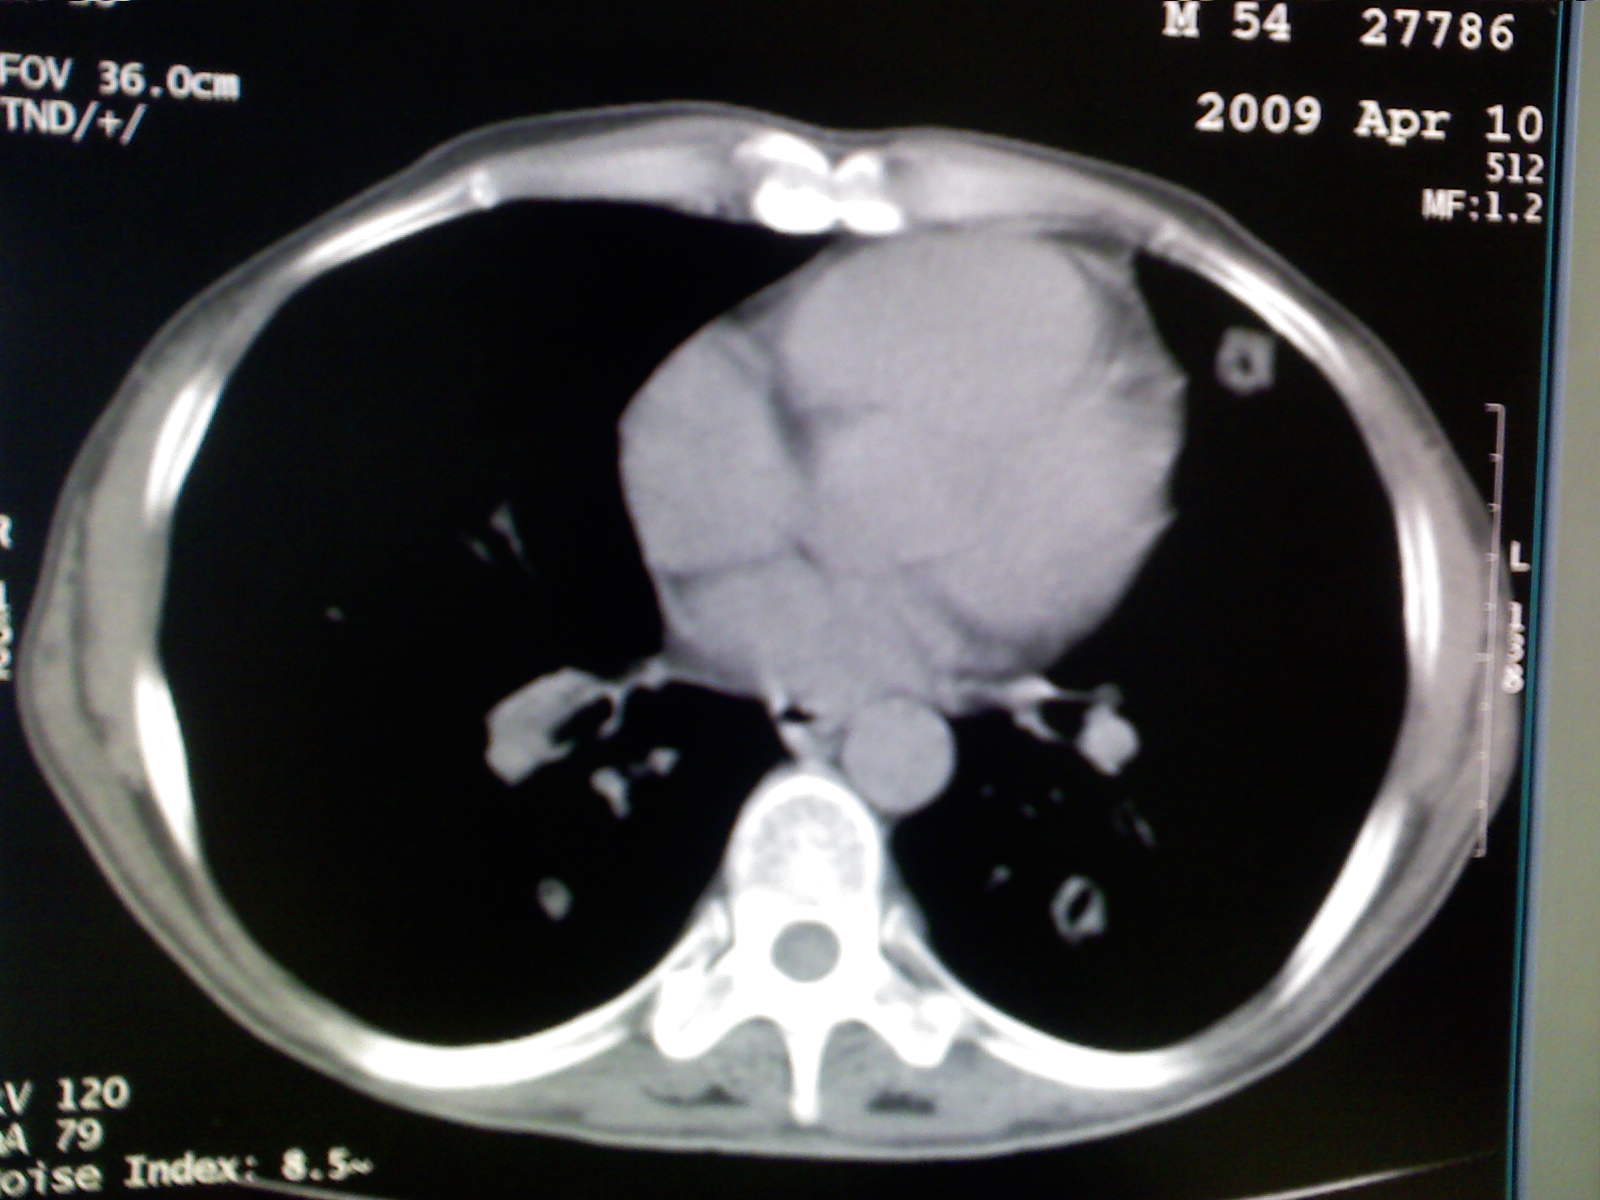

以下是引用卜一在2009-4-11 15:50:00的发言:[br]双肺继发性肺结核伴空洞形成,不排除合并霉菌感染!(病灶呈多形态 多特征 散在分布)。另:合并支气管扩张征伴感染!

以下是引用主力军在2009-4-11 15:55:00的发言:[br]两肺继发性肺结核可能性大。

以下是引用康鹏在2009-4-11 16:30:00的发言:[br]双肺继发性肺结核伴空洞形成合并感染[br]支气管扩张合并感染